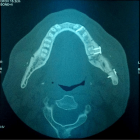

Sagittal split osteotomy (SSO) of the mandible is still an important part of orthognathic surgery, but “bad split” fractures that happen during the surgery are still a big problem. This report describes a rare case of bilateral bad split associated with highly compact mandibular bone (D1–D2 type) in a 53-year-old male undergoing mandibular advancement. The bone was too hard for the piezoelectric and rotary tools to work, and there was very little bleeding. This caused fractures in the cortex and lingual. Postoperative computed tomography confirmed the presence of highly dense bone, correlated with delayed healing and recurrence. Consistent pre-surgical CT scanning for an assessment of the density of the mandibular bone can provide essential information about the potential risk of the osteotomy procedure in the patient. Performing a careful bone quality and density examination pre-operatively will allow the surgeons to select the most appropriate instruments and surgical techniques that will fit the patient’s individual anatomy. Such a point escalates to being very significant when dealing with the geriatric population, as bone density increase can not only alter the fracture behavior but also the recovery process during and after surgery. The inclusion of regular CT-based bone density evaluations into the preoperative routine not only facilitates the anticipation of surgical difficulties but also results in safer and more efficient osteotomies.

Figure 3